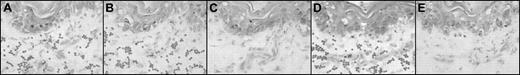

Photomicrographs of sequential sections after skin biopsy from a patient with acute cutaneous GVHD: enzyme and antibody treatments. Representative adherence assay results of experimental manipulations in sequential sections. (A-E) Methyl green-thionin stain; original magnification × 40. Digestion of matrix elements was performed for 30 minutes at 37°C with the following: heparitinase 2 from Flavobacterium heparinum (Calbiochem, La Jolla, CA), 5 mU/mL in buffer (100 mM Na acetate,10 mM Ca acetate, pH 7), keratanase from Pseudomonas species (Calbiochem), 0.5 U/mL in buffer (50 mM Tris HCl, pH 8), hyaluronidase from Streptomyces hyalurolyticus (Sigma, St.Louis, MO), 20 U/mL in PBS buffer. For antibody treatments, assays were performed on alternating sequential sections in the presence of the function-blocking mAb Hermes-1 (10 μg/mL; gift from Dr Brenda Sandmaier, Fred Hutchinson Cancer Research Center) or rat IgG2a isotype antibody (control). Note the characteristic appearance of arcuate, palisading adherent lymphocytes (dark dots) binding to dermal papillary structures (as shown in panels A, B, and D). (A) Heparitinase 2 treatment of skin section. (B) No enzyme treatment; section incubated with PBS (matched control). (C) Hyaluronidase treatment of skin section. (D) Keratanase treatment of skin section. (E) Lymphocytes incubated with anti-CD44 mAb Hermes-1. Notice the absence of binding in the section treated with hyaluronidase (C) and in the section in which the assay was performed in the presence of Hermes-1 (E).

Treatment with heparitinase and keratanase had no effect on the binding of lymphocytes to endothelium, whereas hyaluronidase digestion of all aGVHD skin sections completely blocked lymphocyte adherence to endothelium (Figure 1). In contrast, hyaluronidase treatment of rat lymph node sections did not influence lymphocyte binding to HEV but completely removed HA (as measured by histochemistry) in lymph node and skin sections. Hence, abrogation of binding by hyaluronidase is a consequence of HA digestion and not a general inhibitory effect of enzyme treatment (or digestion conditions) on the capacity of endothelium to support lymphocyte adherence.

Because the principal lymphocyte membrane receptor for HA is CD44,9 we examined its role in binding lymphocytes to dermal endothelium in aGVHD. Hermes-15 completely inhibited lymphocyte binding to all aGVHD skin sections (Figure 1E), whereas isotype control mAb had no effect. Incubation of lymphocytes with Hermes-1 did not alter lymphocyte attachment to rat lymph node HEV, so the effect was not caused by a nonspecific alteration of lymphocyte-binding capabilities.